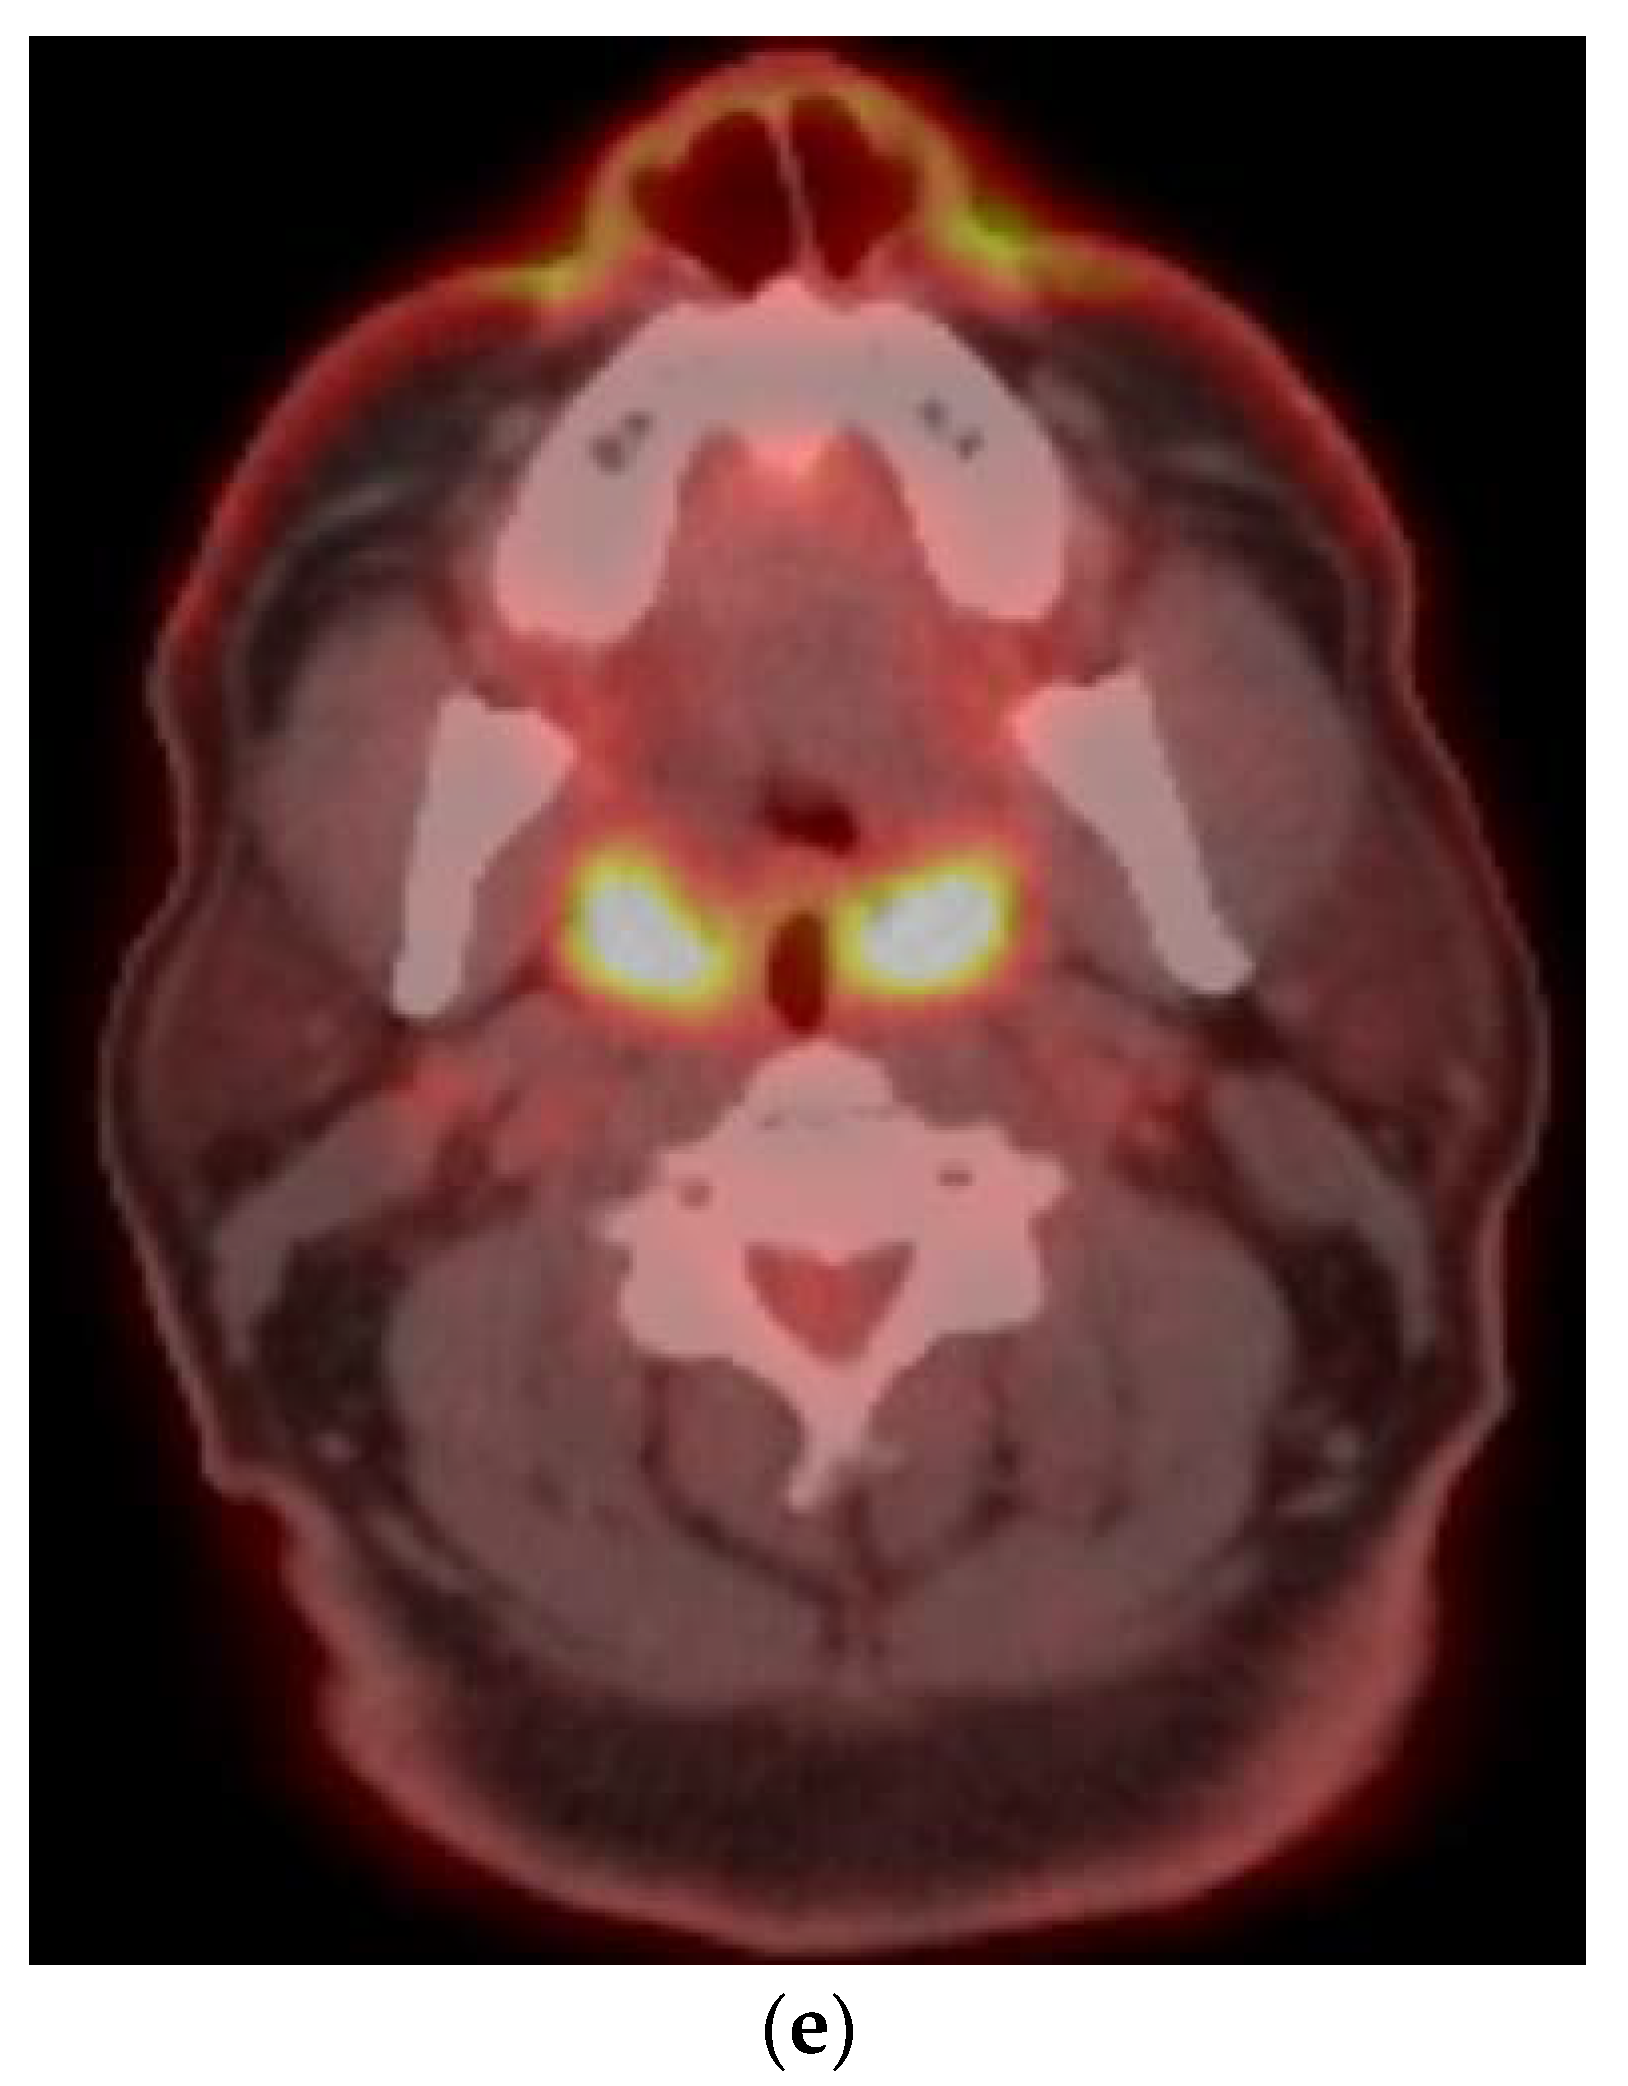

8.1. Initial Staging

- Detection of occult primary lesions in patients presenting with large nodal metastatic masses without identifiable primary cancer on conventional imaging (CT/MRI) before EUA, biopsies, and tonsillectomy.